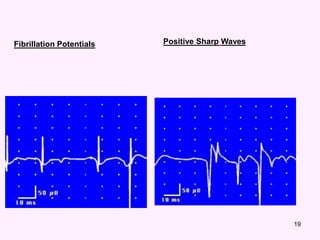

In neurogenic lesion or in active myositis,

the following spontaneous activity is

noted

 Positive sharp wave:

 A small potential of 50 to 100 µV, 5 to 10 msec

duration with abrupt onset and slow outset.

Abnormal MUPs

Fibrillation Potentials Positive Sharp Waves

 Fibrillation potential:

 these are randomly occurring small amplitude

potentials or may appear in runs. The

audioamplifier gives sounds, as if somebody

listen sounds of rains in a tin shade house.

These potentials are generated from the single

muscle fiber of a denervated muscle, possibly

due to denervation hypersensitivity to acetyl

choline.